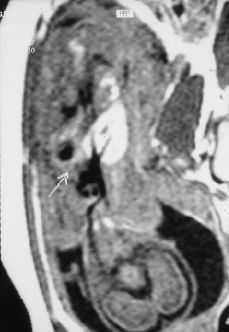

Figura 1. Ecografía fetal: masa hiperecogénica intratorácica.

Primigesta de 22 años con antecedente de síndrome de Wolff-Parkinson-White, ablación con radiofrecuencia en 1996. Con evolución normal del embarazo hasta que en la semana 21, en un control ecográfico se visualiza una masa hiperecogénica, homogénea, de 12 mm en hemitórax izquierdo, en situación retrocardíaca, anterior a la aorta y supradiafragmática, el resto de la anatomía fetal era normal. Placenta normoinserta tipo I y líquido amniótico normal. A continuación se le practica una amniocentesis para estudio de cariotipo fetal con el resultado de 46 XY y los valores de la AFP eran normales.